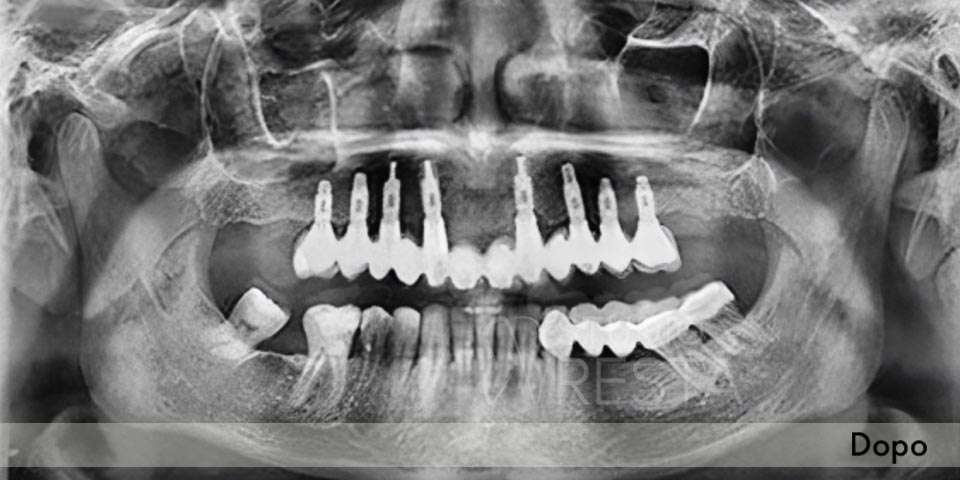

Radiografie

Vedremo le tue vecchie radiografie o te ne faremo delle nuove. Eseguiamo direttamente in studio le radiografie OPT (panoramiche) e/o la Tac Cone Beam 3D

Molti pazienti spesso ci dicono che il loro dentista non ha trovato l'osso. In realtà, alcune volte, l'osso bisogna cercarselo. Questo lo si può fare solo con la Tac Cone Beam 3D attraverso la quale riusciamo a vedere lo spessore, la grandezza, il volume e la profondità dell'osso in cui dovremo inserire gli impianti

Grazie all'immagine della Tac tridimensionale (che eseguiamo in studio) e ad un software particolare studiamo il volume dell'osso disponibile e valutiamo l'inserzione degli impianti utilizzando la tecnica dell'All on Four.